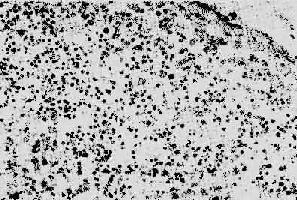

1.淋巴样组织的变化早期及中期,淋巴结肿大。镜下,最初有淋巴滤泡明显增生,生发中心活跃,髓质出现较多浆细胞。随后滤泡的外套层淋巴细胞减少或消失,小血管增生,并有纤维蛋白样物质或玻璃样物质沉积,生发中心被零落分割。副皮质区的淋巴细胞(CD4+细胞)进行性减少,代之以浆细胞浸润。晚期的淋巴结病变,往往尸检时才能看到,呈现一片荒芜,淋巴细胞,包括T、B细胞几乎均消失殆尽,无淋巴滤泡及副皮质区之分,仅有一些巨噬细胞和浆细胞残留(图4-15)。有时特殊染色可显现大量分枝杆菌、真菌等病原微生物,却很少见到肉芽肿形成等细胞免疫反应性病变。

图4-15 AIDS淋巴结

淋巴细胞明显减少,无淋巴滤泡及副皮质区之分